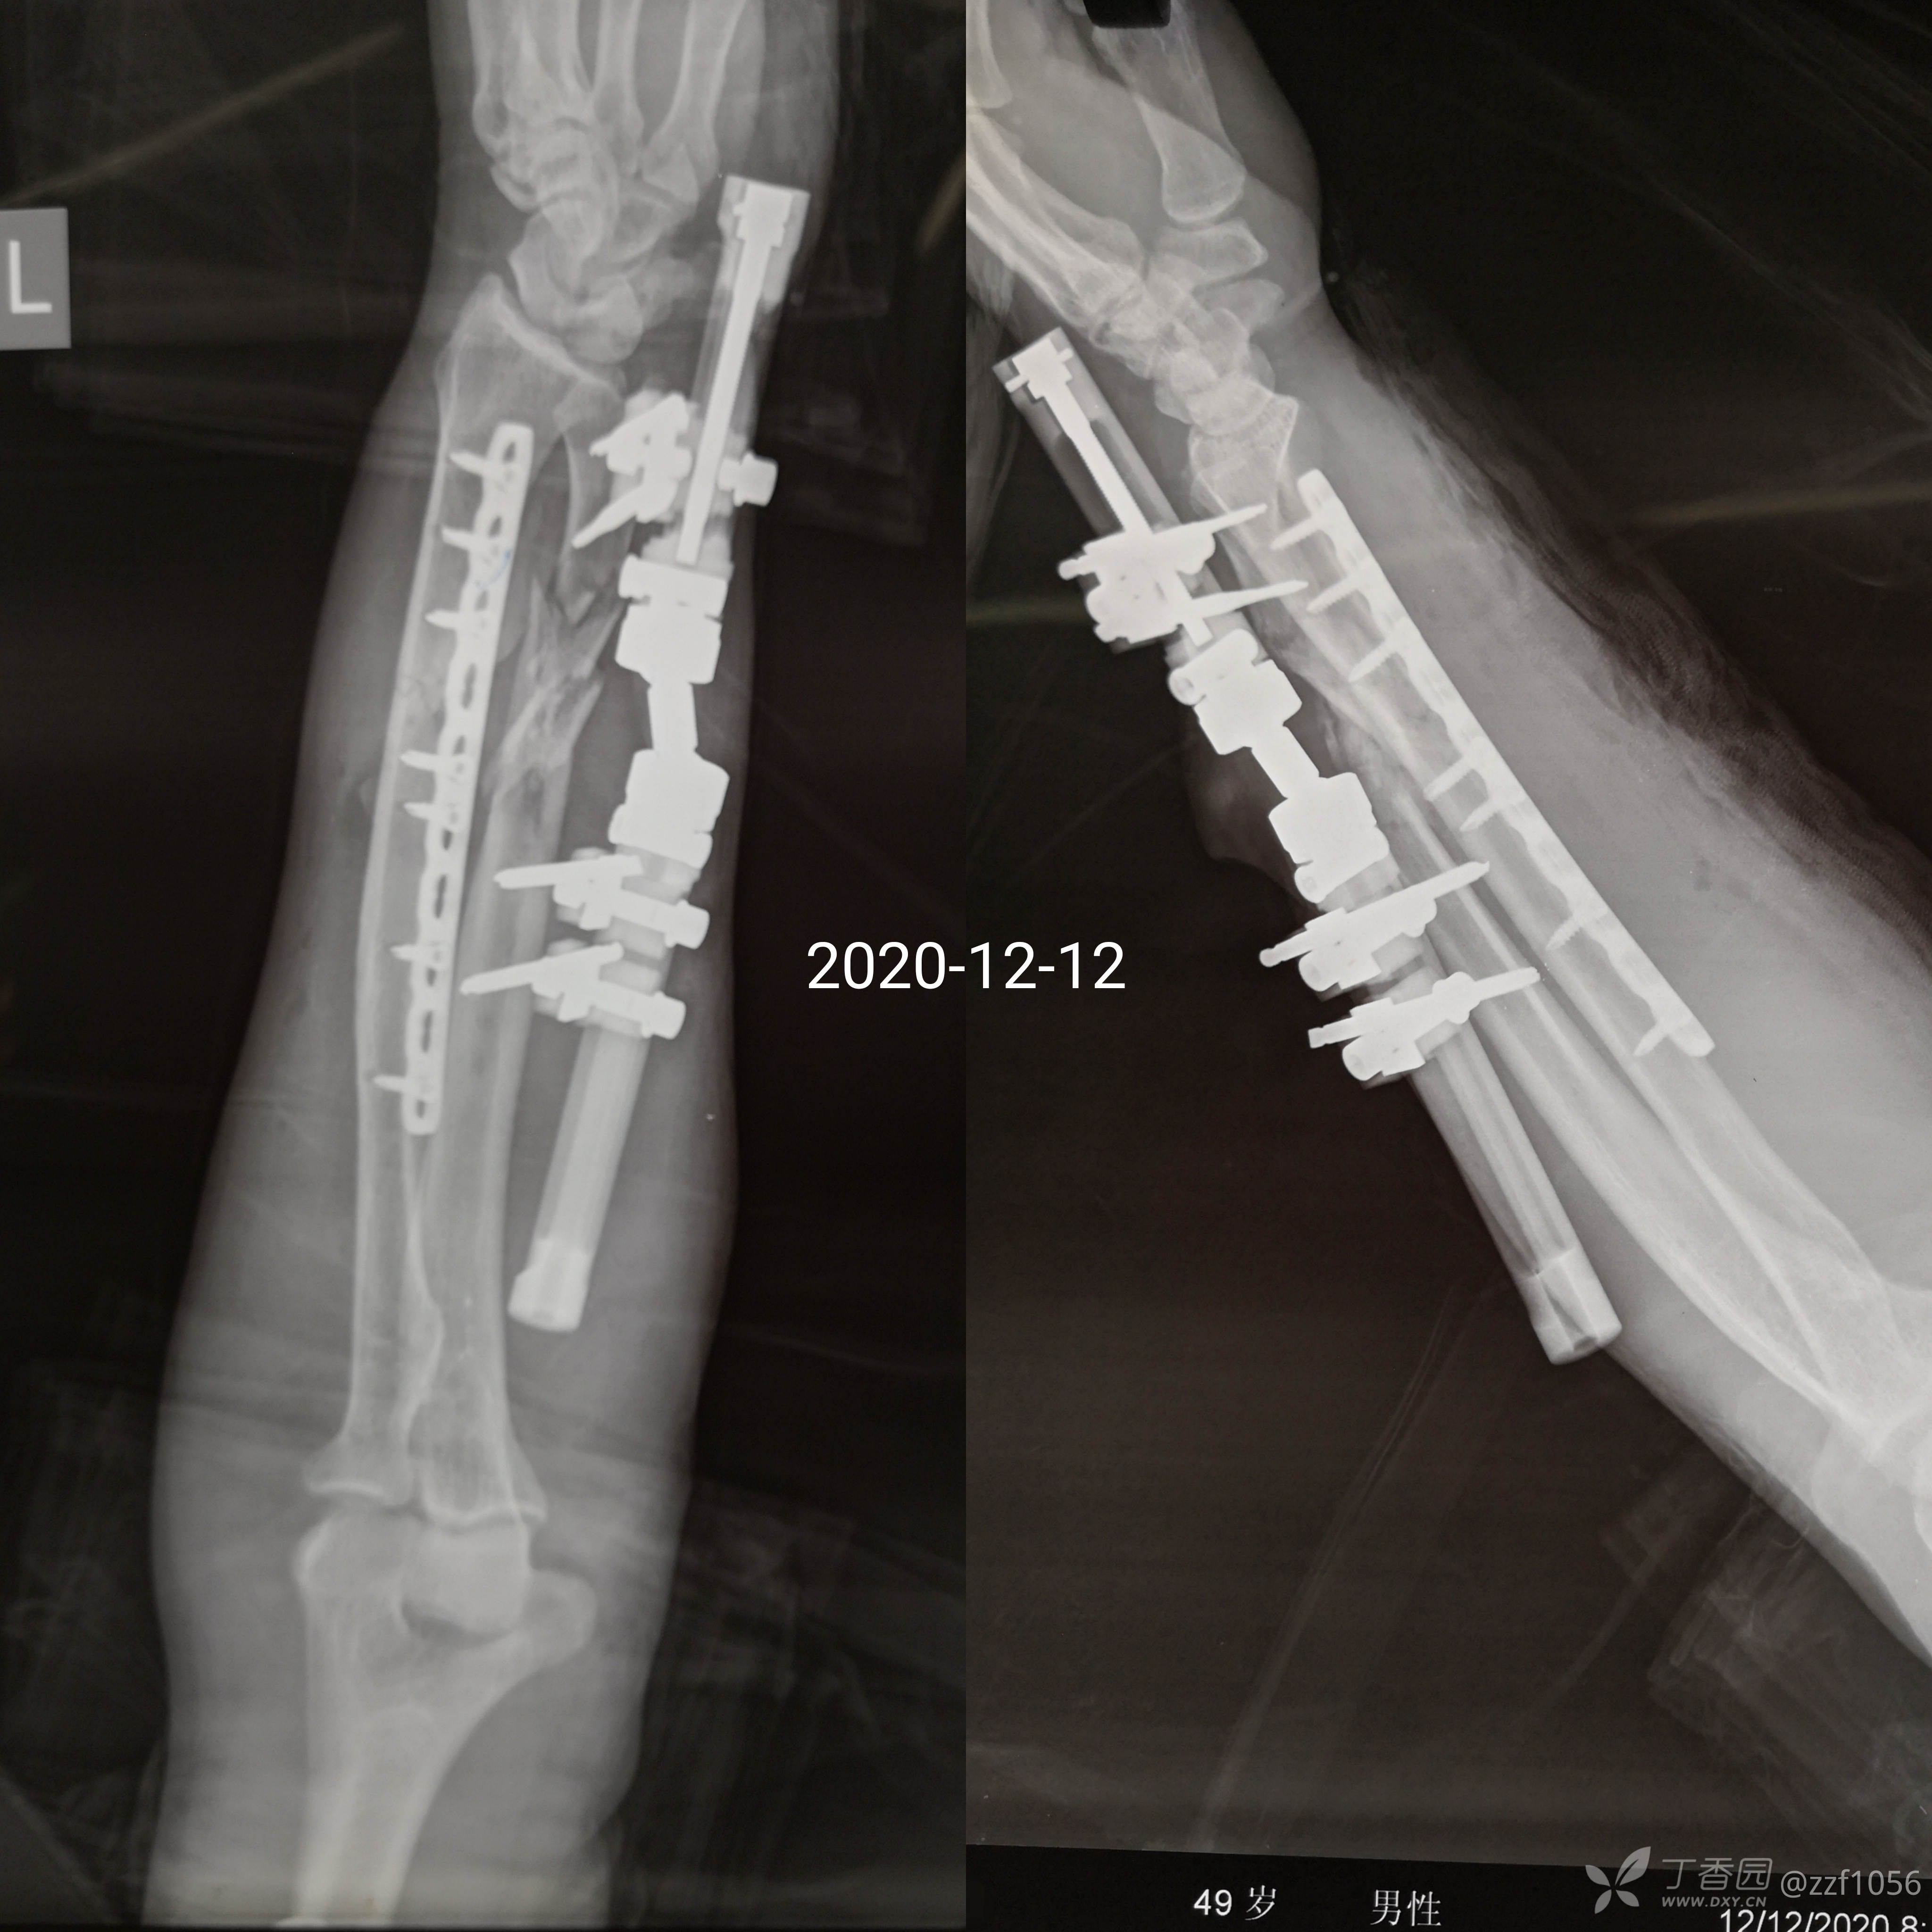

患者王某,男,49岁,因工作时“被机器夹伤左前臂出血疼痛畸形4小时余”自外院转入我院。

入院诊断:左前臂挤压伤,桡骨干骨折,尺骨开放性粉碎性骨折

既往体健,入院后完善相关检查,臂丛麻醉下急诊手术

相关资料如下